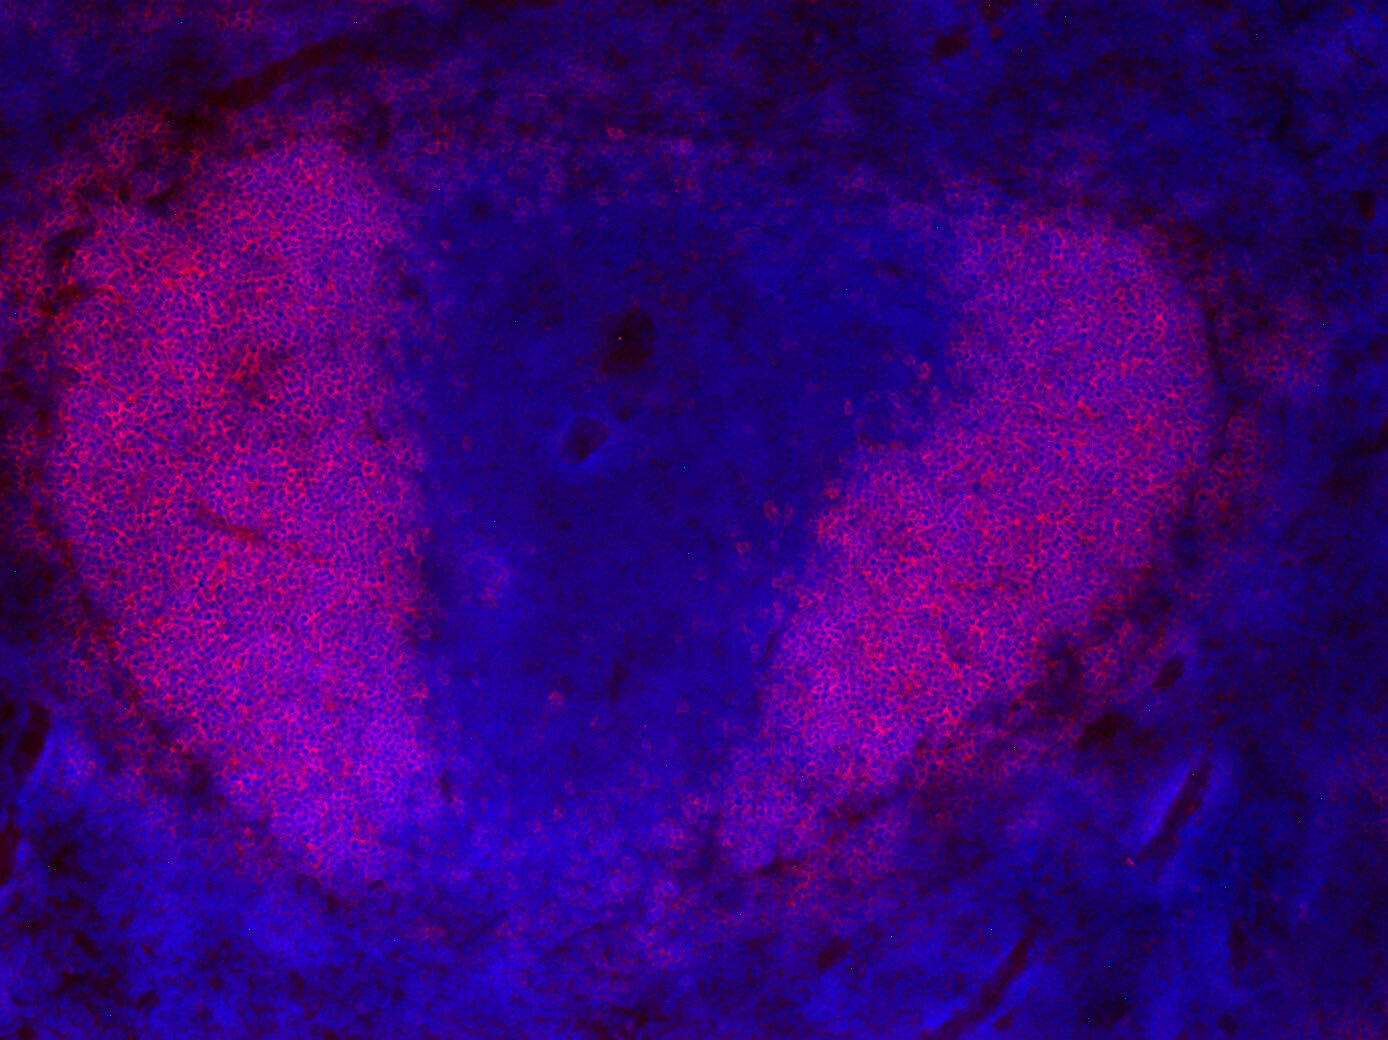

IHC: 1 : 200 gallery

IHC-Fr: 1 : 200 gallery

Immunohistochemistry (IHC) on 4% PFA perfusion fixed tissue with 24h PFA post fixation. Immunoreactivity is usually revealed by fluorescence or a chromogenic substrate. Some antibodies require special fixation methods or antigen retrieval steps. For details, please refer to the ”Remarks” section.